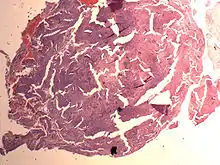

Endometrial Stromal Nodule

It is a subtype of endometrial stromal tumor belonging to the mesenchymal tumors of the main body of the uterus.[1] The appearance of the cells is identical to normal endometrial stromal cells.[1] This can only be differentiated from low-grade endometrial stromal sarcoma by confirming lack of infiltration.

The differential includes cellular leiomyoma. Diagnosis may be aided by immunostaining; endometrial stromal nodules are positive for CD10; leiomyomas are positive for caldesmon and desmin (and sometimes CD10).